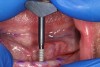

A surgical handpiece was used to perforate the mucosa and develop the osteotomy. The use of a transmucosal or “flapless” osteotomy is a well-established approach for the placement of narrow-diameter implants.22 If needed, as in the case of a surgical complication, a full-thickness mucoperiosteal flap can be developed, which will aid in visualizing the mandible. This requires great care so as not to disturb underlying structures. In this case a 1.2-mm-diameter twist drill running at 1200 rpm brought the osteotomy to a depth of 10 mm (Figure 3), which was dictated by the size of the selected implants. With practice, the clinician can create osteotomies that do not perforate the lingual or buccal cortical plates. This is done by assessing the vertical orientation of the bone by using a free hand to detect its buccal angulation. Interpreting the cross-sectional images is essential. If this is beyond the capabilities of the clinician or if the risk of perforation is great, a pre-drilled surgical guide of a flapped approach can be used for this step. Angulation pins or semi-inserted implants can be placed in shallow osteotomies to verify their orientation and check inter-implant parallelism.

Fig 3. Simplified “flapless” 1.2-mm-wide and 10-mm-deep osteotomy using surgical handpiece and copious irrigation at 1200 rpm. The underlying bone shape is felt with the non-dominant hand to guide handpiece angulation.

Figure 3